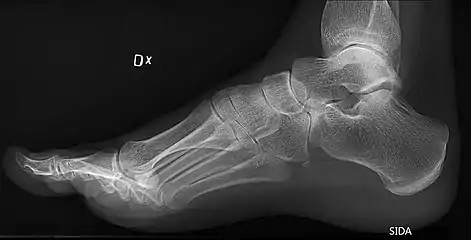

On weightbearing projectional radiography, pes cavus can be diagnosed and graded by several features, the most important being medial peritalar subluxation, increased calcaneal pitch (variable) and abnormal talar-1st metatarsal angle (Meary's angle).[14] Medial peritalar subluxation can be demonstrated by a medially rotated talonavicular coverage angle.[14]

Same lateral X-ray showing the measurement of Meary's angle, which is the angle between the long axis of the talus and first metatarsal bone.[14] This example is slightly convex downward. An angle greater than 4° convex upward is considered pes cavus.[14]

Foot with pes cavus (and os peroneum).